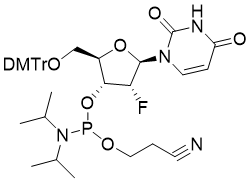

馬鞍山致研生物醫(yī)藥科技有限公司成立于馬鞍山市鄭浦港新區(qū)現(xiàn)代產(chǎn)業(yè)園。公司專(zhuān)注于生物小分子、醫(yī)藥中間體相關(guān)產(chǎn)品的研發(fā)和生產(chǎn),產(chǎn)品主要包括DNA亞磷酰胺單體、RNA亞磷酰胺單體、特殊單體以及按照客戶(hù)要求定制的RNA和DNA,并且公司提供定制合成等方面的研究服...

馬鞍山致研生物醫(yī)藥科技有限公司成立于馬鞍山市鄭浦港新區(qū)現(xiàn)代產(chǎn)業(yè)園。公司專(zhuān)注于生物小分子、醫(yī)藥中間體相關(guān)產(chǎn)品的研發(fā)和生產(chǎn),產(chǎn)品主要包括DNA亞磷酰胺單體、RNA亞磷酰胺單體、特殊單體以及按照客戶(hù)要求定制的RNA和DNA,并且公司提供定制合成等方面的研究服...